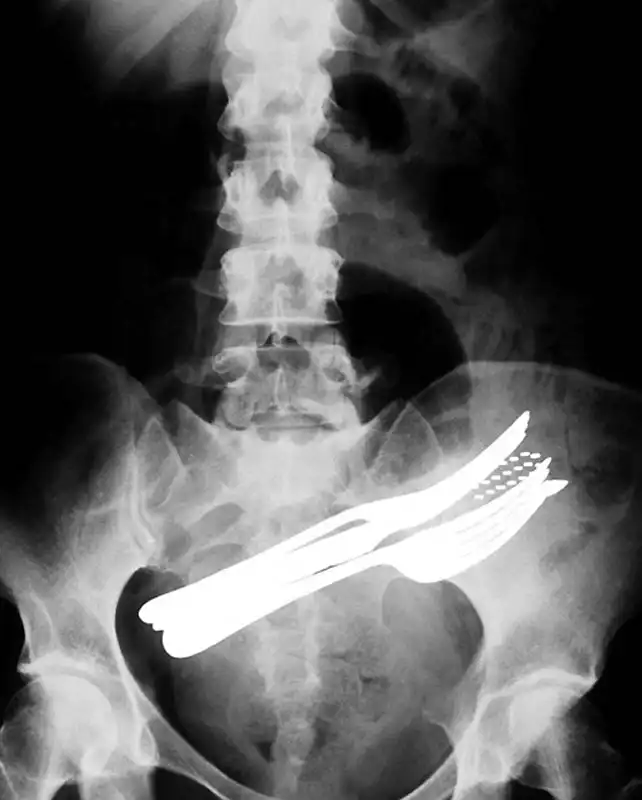

Хирургические ножницы, случайно забытые в теле пациентки после операции. Ножницы были обнаружены лишь через 18 месяцев после операции, т.к. женщина жаловалась на постоянную боль в кишечнике.